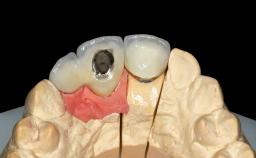

A 45-year-old woman was referred for management of an infection associated with two implant-supported crowns replacing the maxillary central incisors. Two tissue-level implants had been placed and restored with cemented single metal-ceramic crowns in those sites 4 years previously. The patient presented with a draining sinus (i.e. a pathological duct from an abscess cavity to a surface) 3 mm from the midfacial peri-implant mucosal margin of the maxillary right implant crown. She was in good general health, did not smoke, showed a good oral hygiene status, and had no history of periodontal disease. The implants were well positioned. While the patient was very satisfied with the appearance of her crowns, she had noted that the peri-implant soft tissue had receded since their insertion and was concerned about the possibility of further recession.

Retention | Cemented, with prosthesis margin < 3mm submucosal Cemented, with prosthesis margin < 3mm submucosal |

Provisional Implant-Supported Prosthesis | Prosthodontic margin < 3 mm apical to mucosal crest Prosthodontic margin < 3 mm apical to mucosal crest |